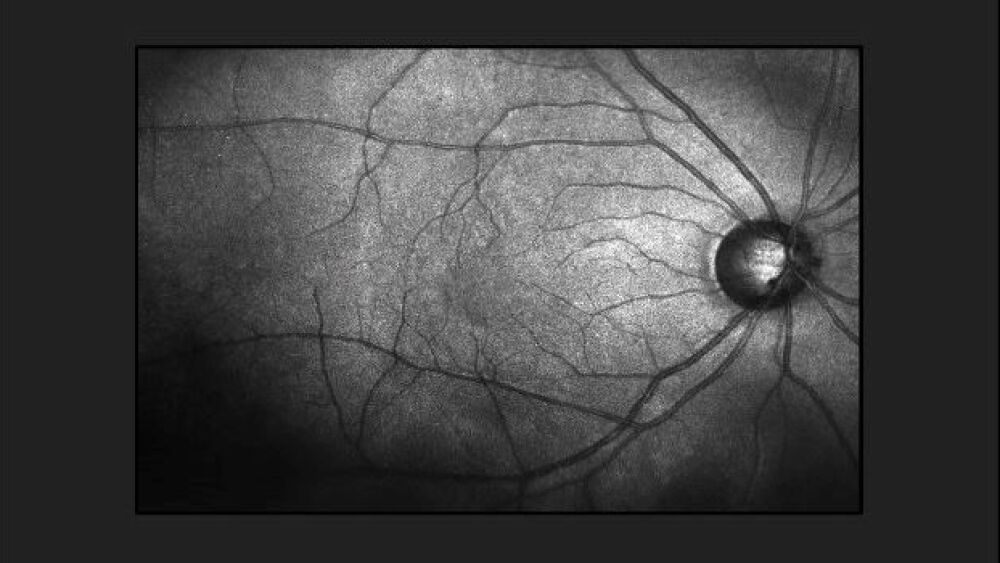

On Thursday, Redwood City, Calif.-based Adverum announced that a review of two separate studies assessing ADVM-022 revealed marked differences in safety for patient populations. Adverum has been studying ADVM-022 in DME as well as wet age-related macular degeneration (wet AMD). Adverum said data from the INFINITY study in DME raised concerns about safety, especially in the high doses of the medication. As a result, the company is suspending its study of ADVM-022 in DME. Specifically, Adverum cited toxicity concerns it had “not seen before in ocular gene therapy or anti-VEGF treatment” in patients with DME.

ADVM-022 is a gene therapy that harnesses Adverum’s propriety vector capsid, AAV.7m8. The therapy is delivered via a single intravitreal (IVT) injection and is designed to reduce the burden of frequent anti-VEGF injections and improve real-world vision outcomes for patients. ADVM-022 earned Fast Track Designation from the U.S. Food and Drug Administration for wet AMD.

The company noted that both wet AMD and DME have different pathophysiological causes with different risk factors. Although they have not determined the cause of the toxicity concerns in DME patients, Adverum noted that diseases have multiple underlying comorbidities, such as severe vascular disease. The vascular issues may have contributed to inflammatory factors that caused an increase in vascular permeability and disrupted the blood-ocular barrier in DME patients.